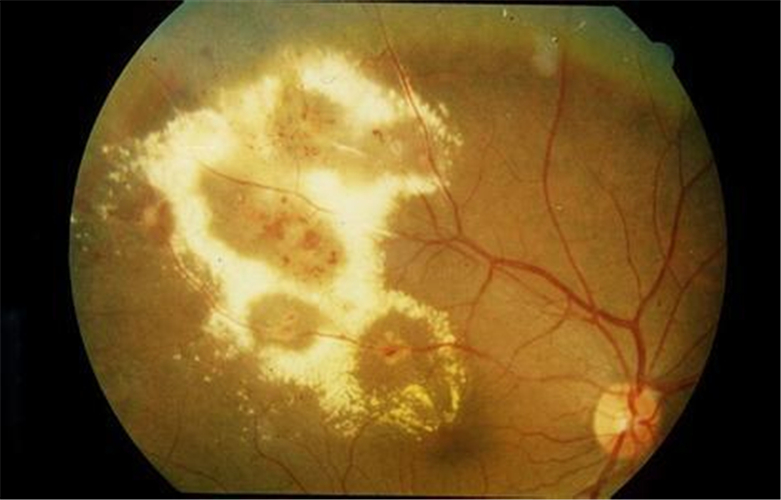

增值引發視網膜脫落

增值併發視網膜脫落

增生引起視網膜脫落

增生併發視網膜脫落